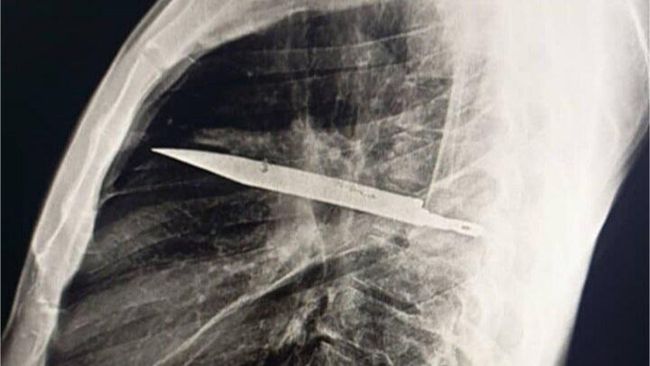

Penampakan pisau menancap di dada pasien pria.(Foto: Journal of Surgical Case Reports)

Mengutip detikHealth, pasien yang identitasnya dirahasiakan itu awalnya datang ke rumah sakit karena merasakan nyeri dan keluarnya nanah di sekitar puting kanan. Saat menjalani pemeriksaan rontgen, dokter dibuat terkejut. Hasil pemindaian menunjukkan adanya pisau yang tertinggal di dalam dada pasien.

"Rontgen dada lateral awal menunjukkan adanya benda logam tersangkut di bagian tengah dada, dengan bayangan samar di sekitarnya yang mengindikasikan hematoma terlokalisasi kronis yang mengeluarkan cairan, atau fibrosis pascatrauma, kemungkinan besar akibat luka tusukan pisau pasien," tulis dokter dalam jurnal, dikutip dari News18, Selasa (19/8/2025).